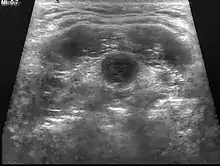

غالباً ما يتم تشخيص الكيس الدرقي اللساني بالفحص السريري عن طريق الطبيب. من المهم أن يتم التأكد من وجود أي نسيج درقي متواجد داخل الكيس، والذي سيحدد درجة حدة الحالة التي يتم التعامل معها.

| الأشعة فوق الصوتية | ترسل الأشعة فوق الصوتية موجات عالية التردد لخلق صور للأوعية الدموية والأنسجة والأعضاء للكشف عن الكتلة والأنسجة للغدة الدرقية |